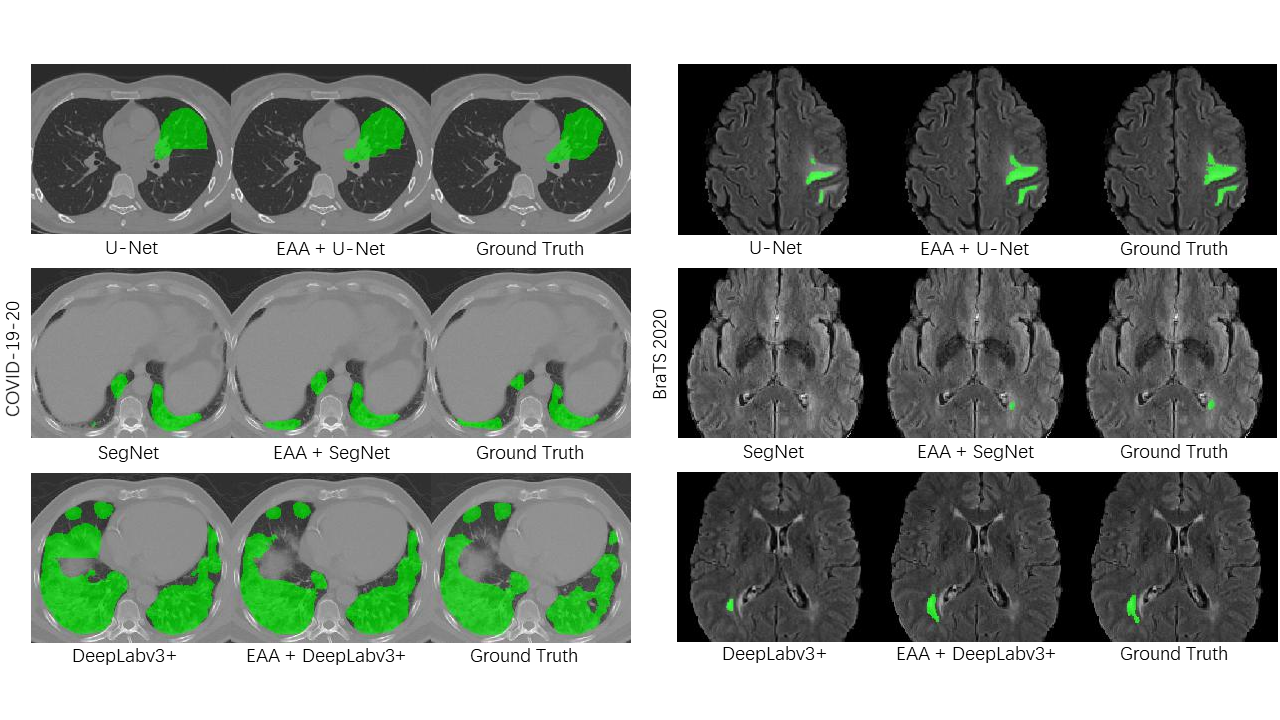

Refer to caption

Fig. 6: Qualitative comparison against other methods. The segmentation results of the lesion area are indicated in green color. Our method improve the quality of segmentation edges.

Table 2 gives the segmentation results on BraTS 2020. Note that the segmentation performance of EAA-Net is better than corresponding autoencoder architecture. In the meantime, the number of parameters of EAA-Net is less than the corresponding autoencoder architecture. Table 2 shows that our method is superior to the segmentation methods without reconstruction sub-network on the HD95. Hausdorff distance is more sensitive to boundaries. Therefore, Hausdorff distance is often used for image segmentation tasks that pay attention to edge details. The Dice coefficient is the most frequently used metric in medical image competitions. It is a collective similarity metric, usually used to calculate the similarity of two samples. The Dice coefficient is more sensitive to the internal filling of the mask. The accurate segmentation of edge details also makes the dice coefficient of our framework higher than the corresponding backbone network. Experimental results indicate that EAA-Net significantly improves the segmentation efficiency of the autoencoder architectures. This trend also appears in lung lesion segmentation tasks, as shown in Table 3. The qualitative comparison of the proposed EAA-Net is shown in Fig. 3. The edge segmentation results obtained by using EAA-Net are significantly better than the corresponding backbone network. This result not only appeared in the segmentation task of lung lesions, but also appeared in the segmentation task of brain tumors.